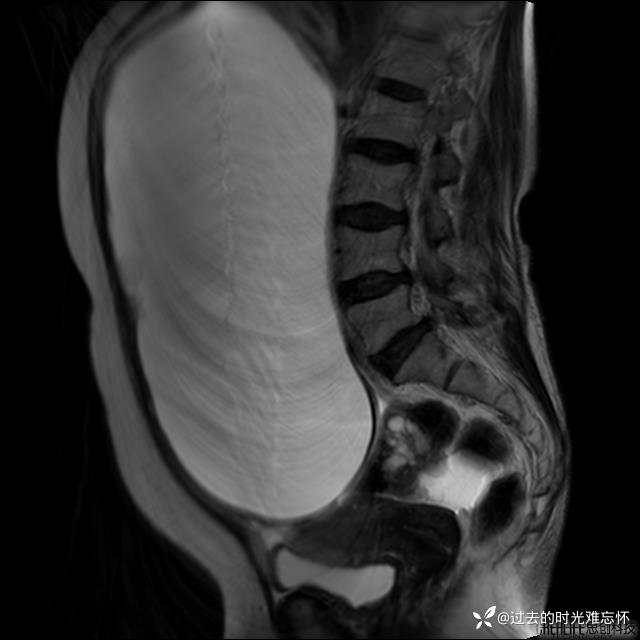

患者性别:女

患者年龄:65岁

主诉: 发现腹部隆起半年余。无其他明显不适。

浆液性囊腺瘤 (22)